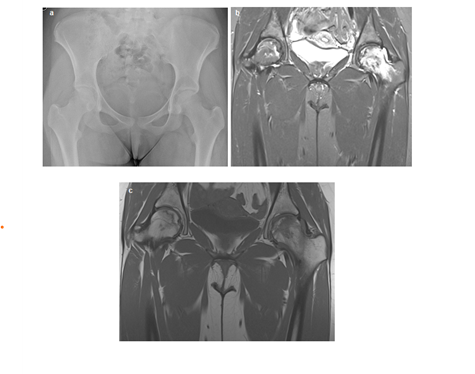

6 months later, the patient started complaining increasing hip joint bilateral pain with bilateral limitation in the inward rotation of the hips. Pelvic X-ray was conducted with normal findings. Therefore, pelvic Magnetic Resonance Imaging (MRI) performed one week after the onset of the symptoms, showed bilateral avascular necrosis of the femoral head (left > right) with preserved height and morphology of both femoral heads (Figure 1).

Figure 1 : (a) Hip X-ray at the onset of AVN, revealing no significant bony abnormalities. (b, c) Subsequent coronal Magnetic Resonance Imaging (MRI) performed within days, including STIR (b) and T1-weighted (T1W) (c) sequences, demonstrating diffuse bone marrow edema in both femoral heads, with greater involvement on the left. Notably, the left femoral head exhibits a serpiginous line of hyperintensity, the ‘double line sign’, indicative of subchondral collapse.”